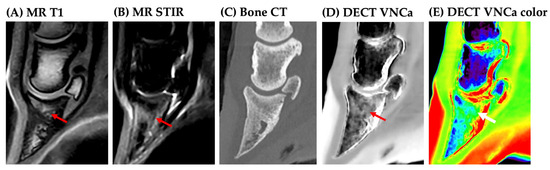

1. Introduction